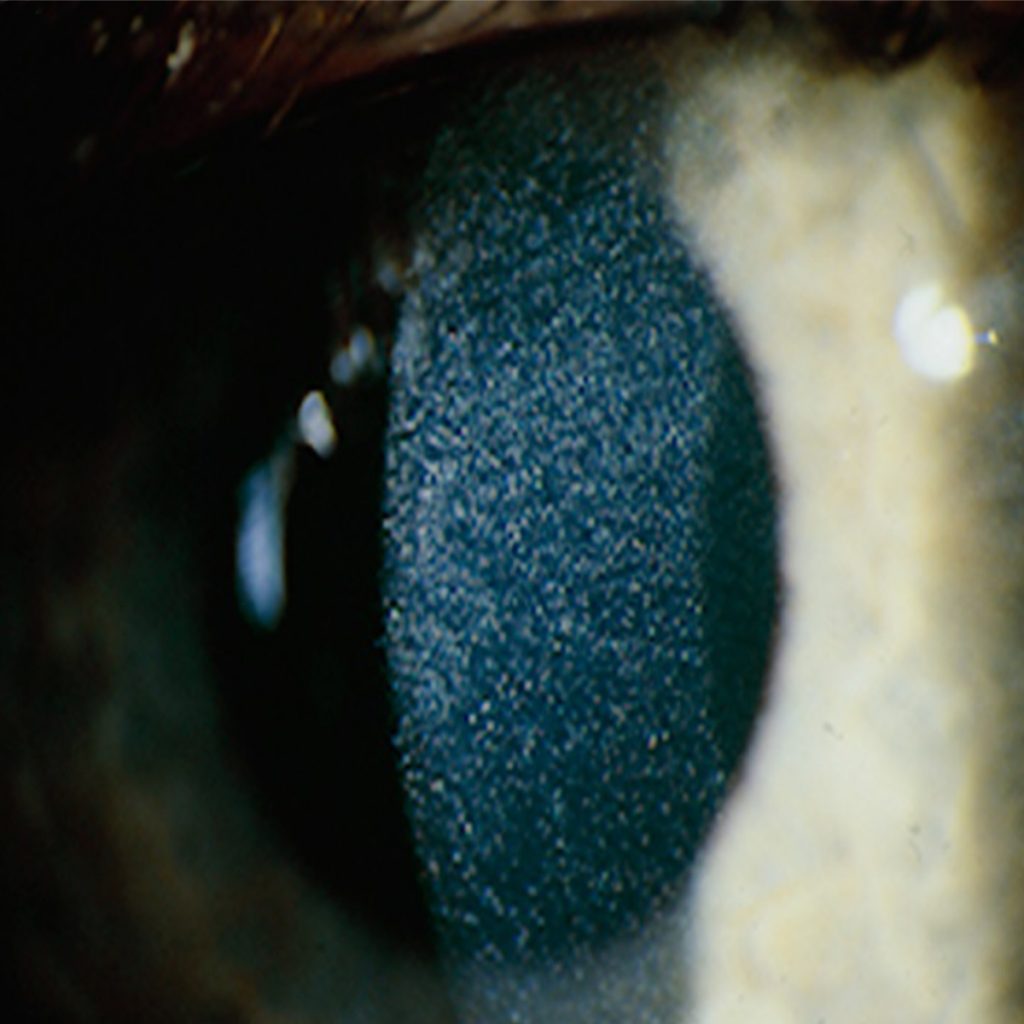

Eye meeting

October 2015

Infantile nephropathic cystinosis is a multi-organ disease.